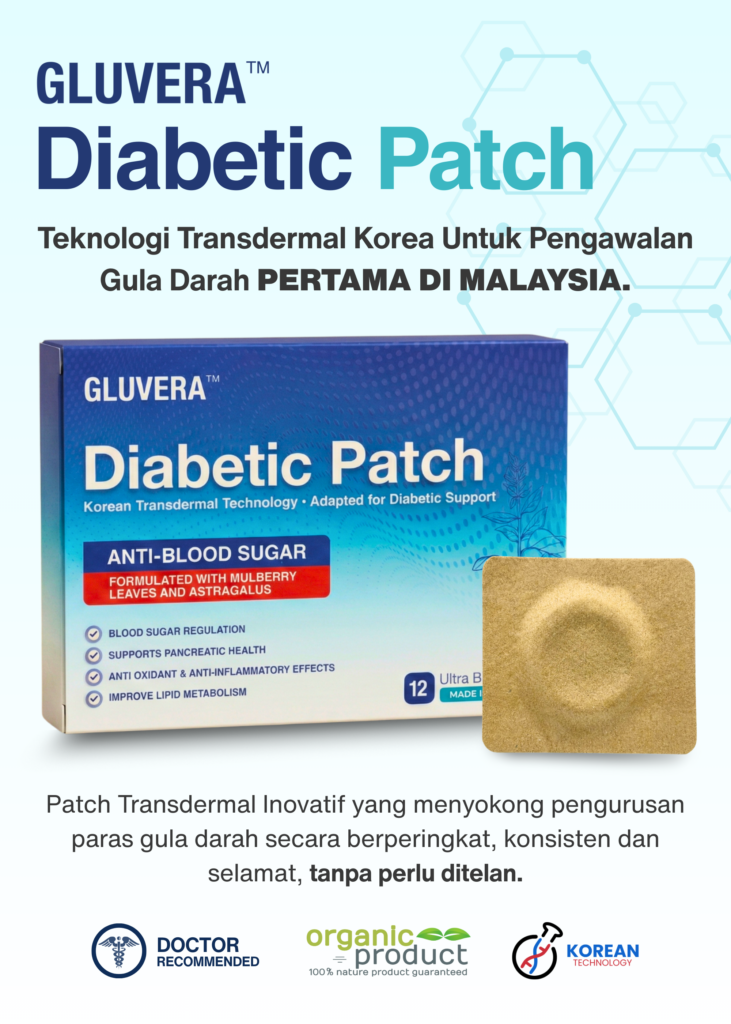

TEKNOLOGI TRANSDERMAL ATASI GULA DALAM DARAH NO.1 DI MALAYSIA